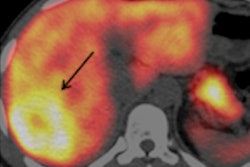

"The challenge is to be able to detect liver steatosis and to distinguish patients with simple steatosis from those who evolve to NASH that associates steatosis with inflammation and a ballooning of the hepatocytes and may evolve to cirrhosis and/or hepatocellular carcinoma," she said. "Moreover, NASH is associated with diabetes mellitus [type] 2 and metabolic syndromes, which require specific management."

Ultrasound of a 14-year-old girl with severe obesity (body mass index [BMI], 42 kg/m2). There is hepatomegaly associated with increased liver echogenicity when compared to the right kidney and attenuation corresponding to severe steatosis. Below, the same patient shows increased liver-to-kidney ratio. All images courtesy of Dr. Stéphanie Franchi-Abella, PhD.Early detection is important, as diet may reverse the process at the early phase of the disease. Yet the detection and quantification of liver fat content and associated fibrosis and inflammation, mandatory in the diagnosis of NASH, remain challenging in children; B-mode ultrasound remains relatively limited for the diagnosis of liver steatosis, as fat content should be more than 20%, but quantification is not yet available as a routine clinical tool on ultrasound scanners, according to Franchi-Abella.

Although liver fibrosis evaluation is improving with the use of shear-wave elastography (SWE), it still lacks validation for pediatric use. Meanwhile, MR quantification of steatosis and fibrosis remains difficult in children and less effective than in adults.